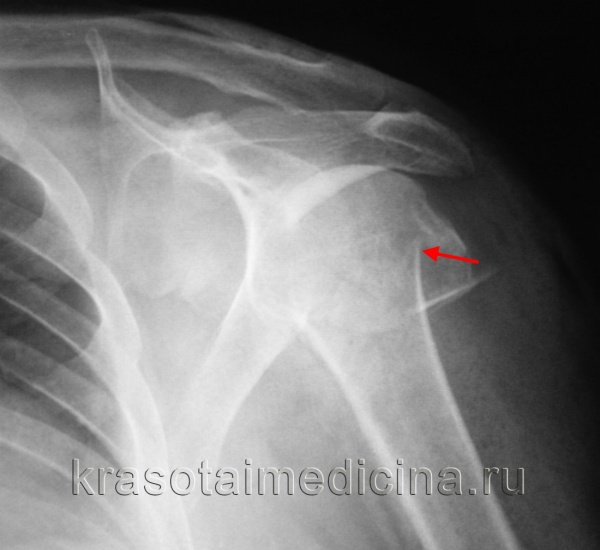

На представленных ниже рентгенограммах локтевого сустава определяется оскольчатый перелом мыщелков левого плеча с 4 большими фрагментами.